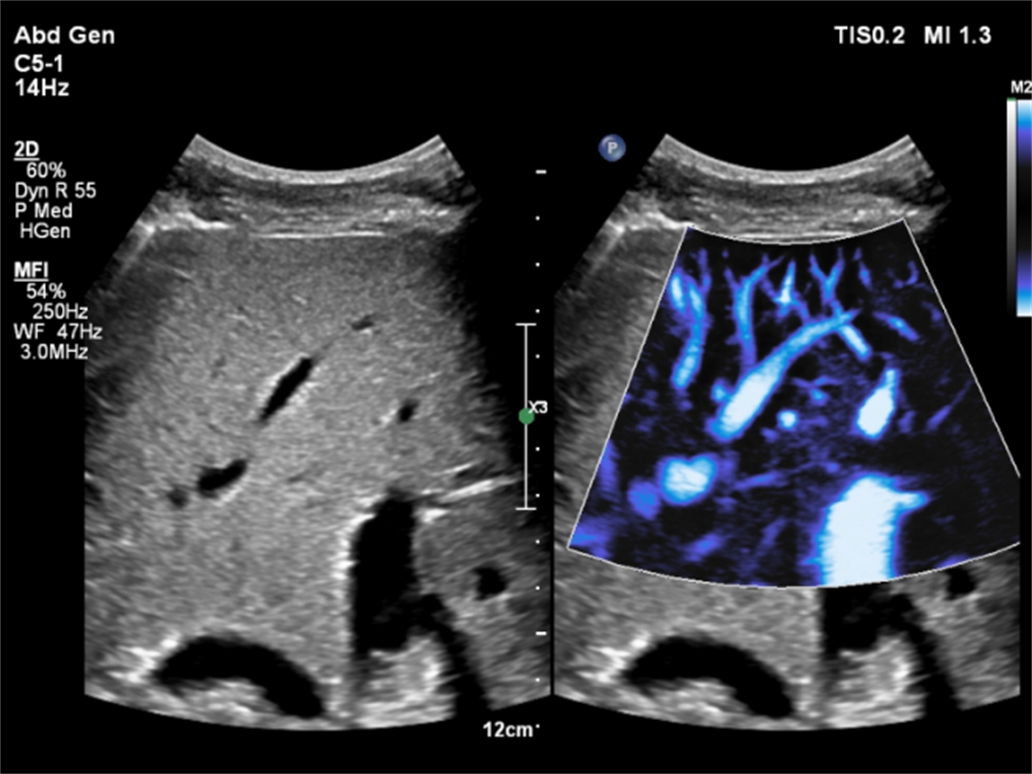

该超声诊断系统采用了业内领先的nSightPro平台、纯净波单晶体探头、微细血流显像等技术,为超声医生诊断提供实时、快速、清晰、内容丰富的超声图像。对小儿、肥胖病人等特殊病患也能提供较好的诊断支持。

EPIQ7设备所采用的C5-1探头融合了差异校正技术的新研发成果,在降低表浅脂肪组织影响的同时提高了深层区域的分辨力,应用大大改善图像质量的纯净波技术,40cm的穿透深度,带来前所未有的视觉体验。100度拓展成像扇角,可以获取更多的图像信息,减少误诊和漏诊,大大缩短检查时间。临床实用性和人体工程学同样是C5-1探头的设计要素。C5-1探头厚度设计精准纤薄,确保能获得优异的肋间声窗,对所有患者都能提供优质的成像性能和方便舒适的可操控性。